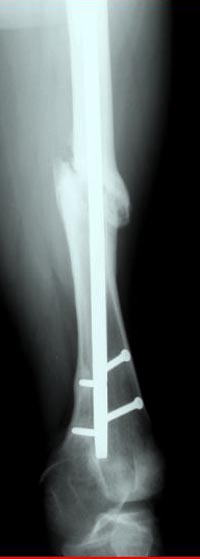

Аппарат Илизарова= Taylor spatial frame

Операцию провели в два этапа, сперва удалили штифт, рассверливание римером на пару мм большего диаметра, определение чувствительности на анаэробную и аэробную культуру (где исследования показали негативный результат чувствительности), через дней десять - начали аппаратную фиксацию.